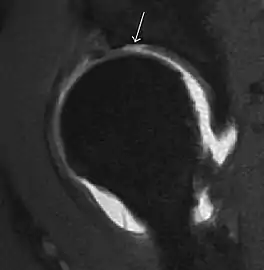

Figure 9:

Sagittal T1 weighted image showing anterosuperior labral tear.[1]